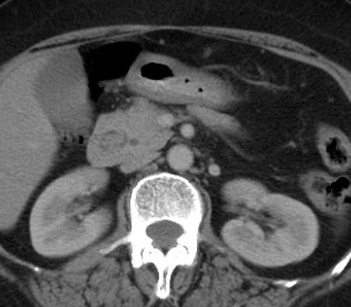

CT